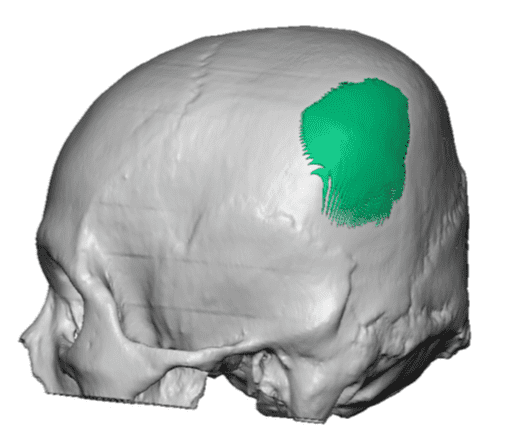

Desire for change of head shape from front view form an inverted V shape to a rounder and wider head shape.

Placement of custom extended forehead-temporal implants through incisions in the crease behind the ear. (he had a prior back of head skull implant which is green in the implant designs and which the head widening implants partially covered it)

Desire for change of head shape from front view form an inverted V shape to a rounder and wider head shape.

Placement of custom extended forehead-temporal implants through incisions in the crease behind the ear. (he had a prior back of head skull implant which is green in the implant designs and which the head widening implants partially covered it)